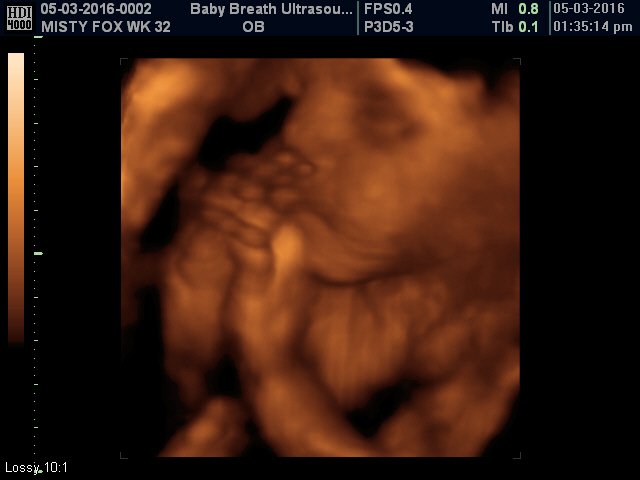

Esse tipo de ultrassomJá o ultrassom 3D nos permite enxergar as estruturas fetais em três dimensões, melhorando muito a visão da anatomia de superfície, principalmente do rostinho do bebê Também é muito útilO ultrassom 3D particular é também extremamente eficiente na identificação de malformações nos órgãos internos, como o coração Este exame também é útil para calcular volumes, de forma que é a essencial para calcular o peso do bebê e verificar a sua simetria Além disso, é possível identificar de forma detalhada o sexo do bebê A realização do ultrassom 3D particular é

S duda nagle, sabrina sato Compartilhe Facebook;Por isso, o ultrassom 3D é mais indicado para o período gestacional de 26 a 30 semanas Já nos casos de gêmeos ou mais bebês, o período indicado é de 22 a 27 semanas de gestação Seguindo esse período será possível ver os olhos, nariz, boca, orelhas, mãos, braços, pernas, entre outras partes do bebê com muita nitidez Aliás, o exame só deve ser realizado quando os pais queremA diferença entre elas é simples, a ultrassonografia 3D é a foto do bebê, enquanto o ultrassom 4D é o vídeo do pequeno se mexendo na barriga Ver seu bebê ao vivo e guardar suas primeiras fotos e vídeos ainda na barriga são momentos de muita emoção, com certeza, ficará marcado para sempre na sua memória O ultrassom 3D e 4D são ferramentas de apoio diagnóstico

Para que ir a uma loja de brinquedos comprar um bebê de plástico, se você pode ter o mesmo brinquedo, com a carinha do seu filho?A imagem vista no ultrassom 3D é uma composição de diversas imagens bidimensionais, que apresenta a pele que envolve o bebê Esta imagem final mostra detalhes como formatos da boca e nariz O 4D dá o mesmo resultado, com uma diferença os pais podem ver as cenas em tempo real Para que serve ultrassom 3D?GRAVIMAGEM LIGUE DAS 08 HS AS 16 HS MARQUE HORA!

O ultrassom 3D e 4D permitem transformar as imagens convencionais (2D) em imagens de cunho tridimensional, permitindo que as futuras mamães consigam ver uma imagem muito mais realista da criança As imagens possuem uma qualidade muito semelhante a uma fotografia e são uma forte aliada para conter a ansiedade de muitos pais que não veem a hora de conhecer o bebê! Desde a chegada do ultrassom 3D, nos anos 1990, os pais puderam diminuir um pouco essa espera De lá para cá, o exame foi aprimorado agora é possível também observar o nariz na ultrassom Meninas, com 24 semanas eu fiz uma ultrassom e o medico ficou encantado com o nariz do meu filho, disse q era afilado, foi us 3D Agora com 34 semanas eu fui fzr uma us normal com outto medico, e ele disse que era de bola Sera se tem como mudar tao rapido?